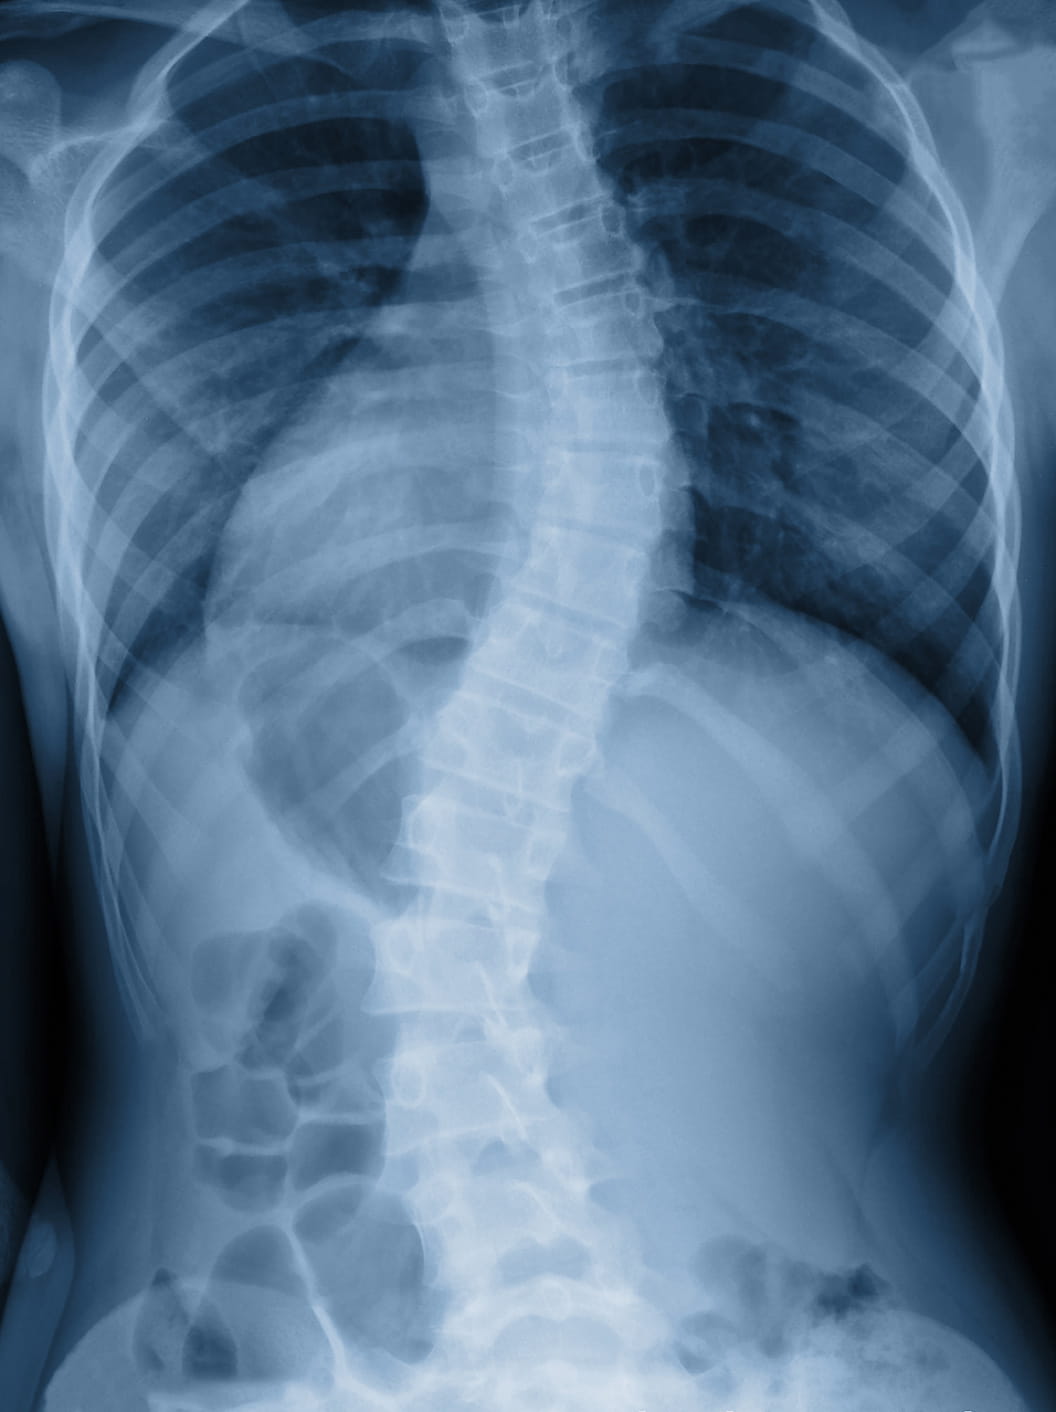

The prognosis and treatment plan for adolescent idiopathic scoliosis (AIS) is explained by David Bumpass, M.D., an orthopedic spine surgeon at Arkansas Children's Hospital.

Scoliosis is the most common type of spinal deformity. Scoliosis is when the spine is abnormally curved. There are several types of scoliosis found in children, the most common of which is adolescent idiopathic scoliosis (AIS). AIS impacts approximately 5% of the population.

Adolescent idiopathic scoliosis (AIS) is an abnormal curve (“S” or “C” shape) of the spine that appears in late childhood or during the adolescent growth spurt. It typically affects children who have no other medical problems. While a family history of scoliosis is common, AIS patients often do not have other family members with the condition.

Scoliosis can be a devastating disease if untreated; however, the current advances in both non-surgical (bracing) and surgical treatment are enabling children with scoliosis to lead fulfilling and active lives.